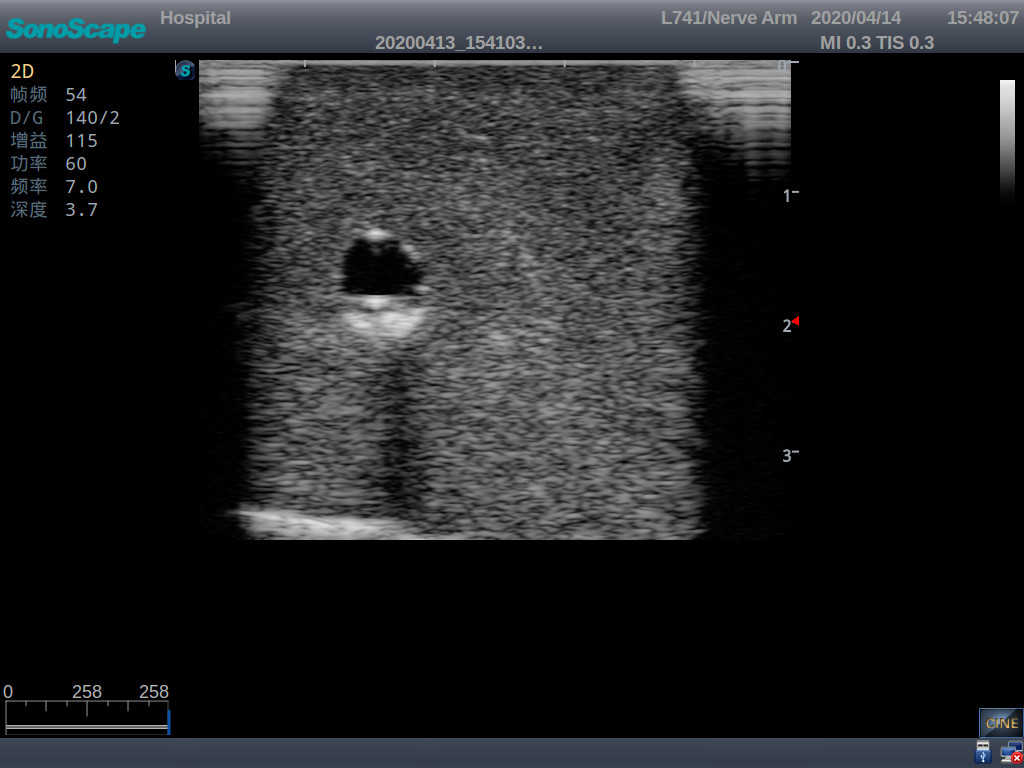

2)   It can be used by real ultrasound machines

3)   Clear and real images of the tissues and organs (basilic vein and superior vena cava)

4)   When conducting vascular puncture, the piercing can be truly felt, and venous blood outflow can be seen

5)   Observe the guide wire marches